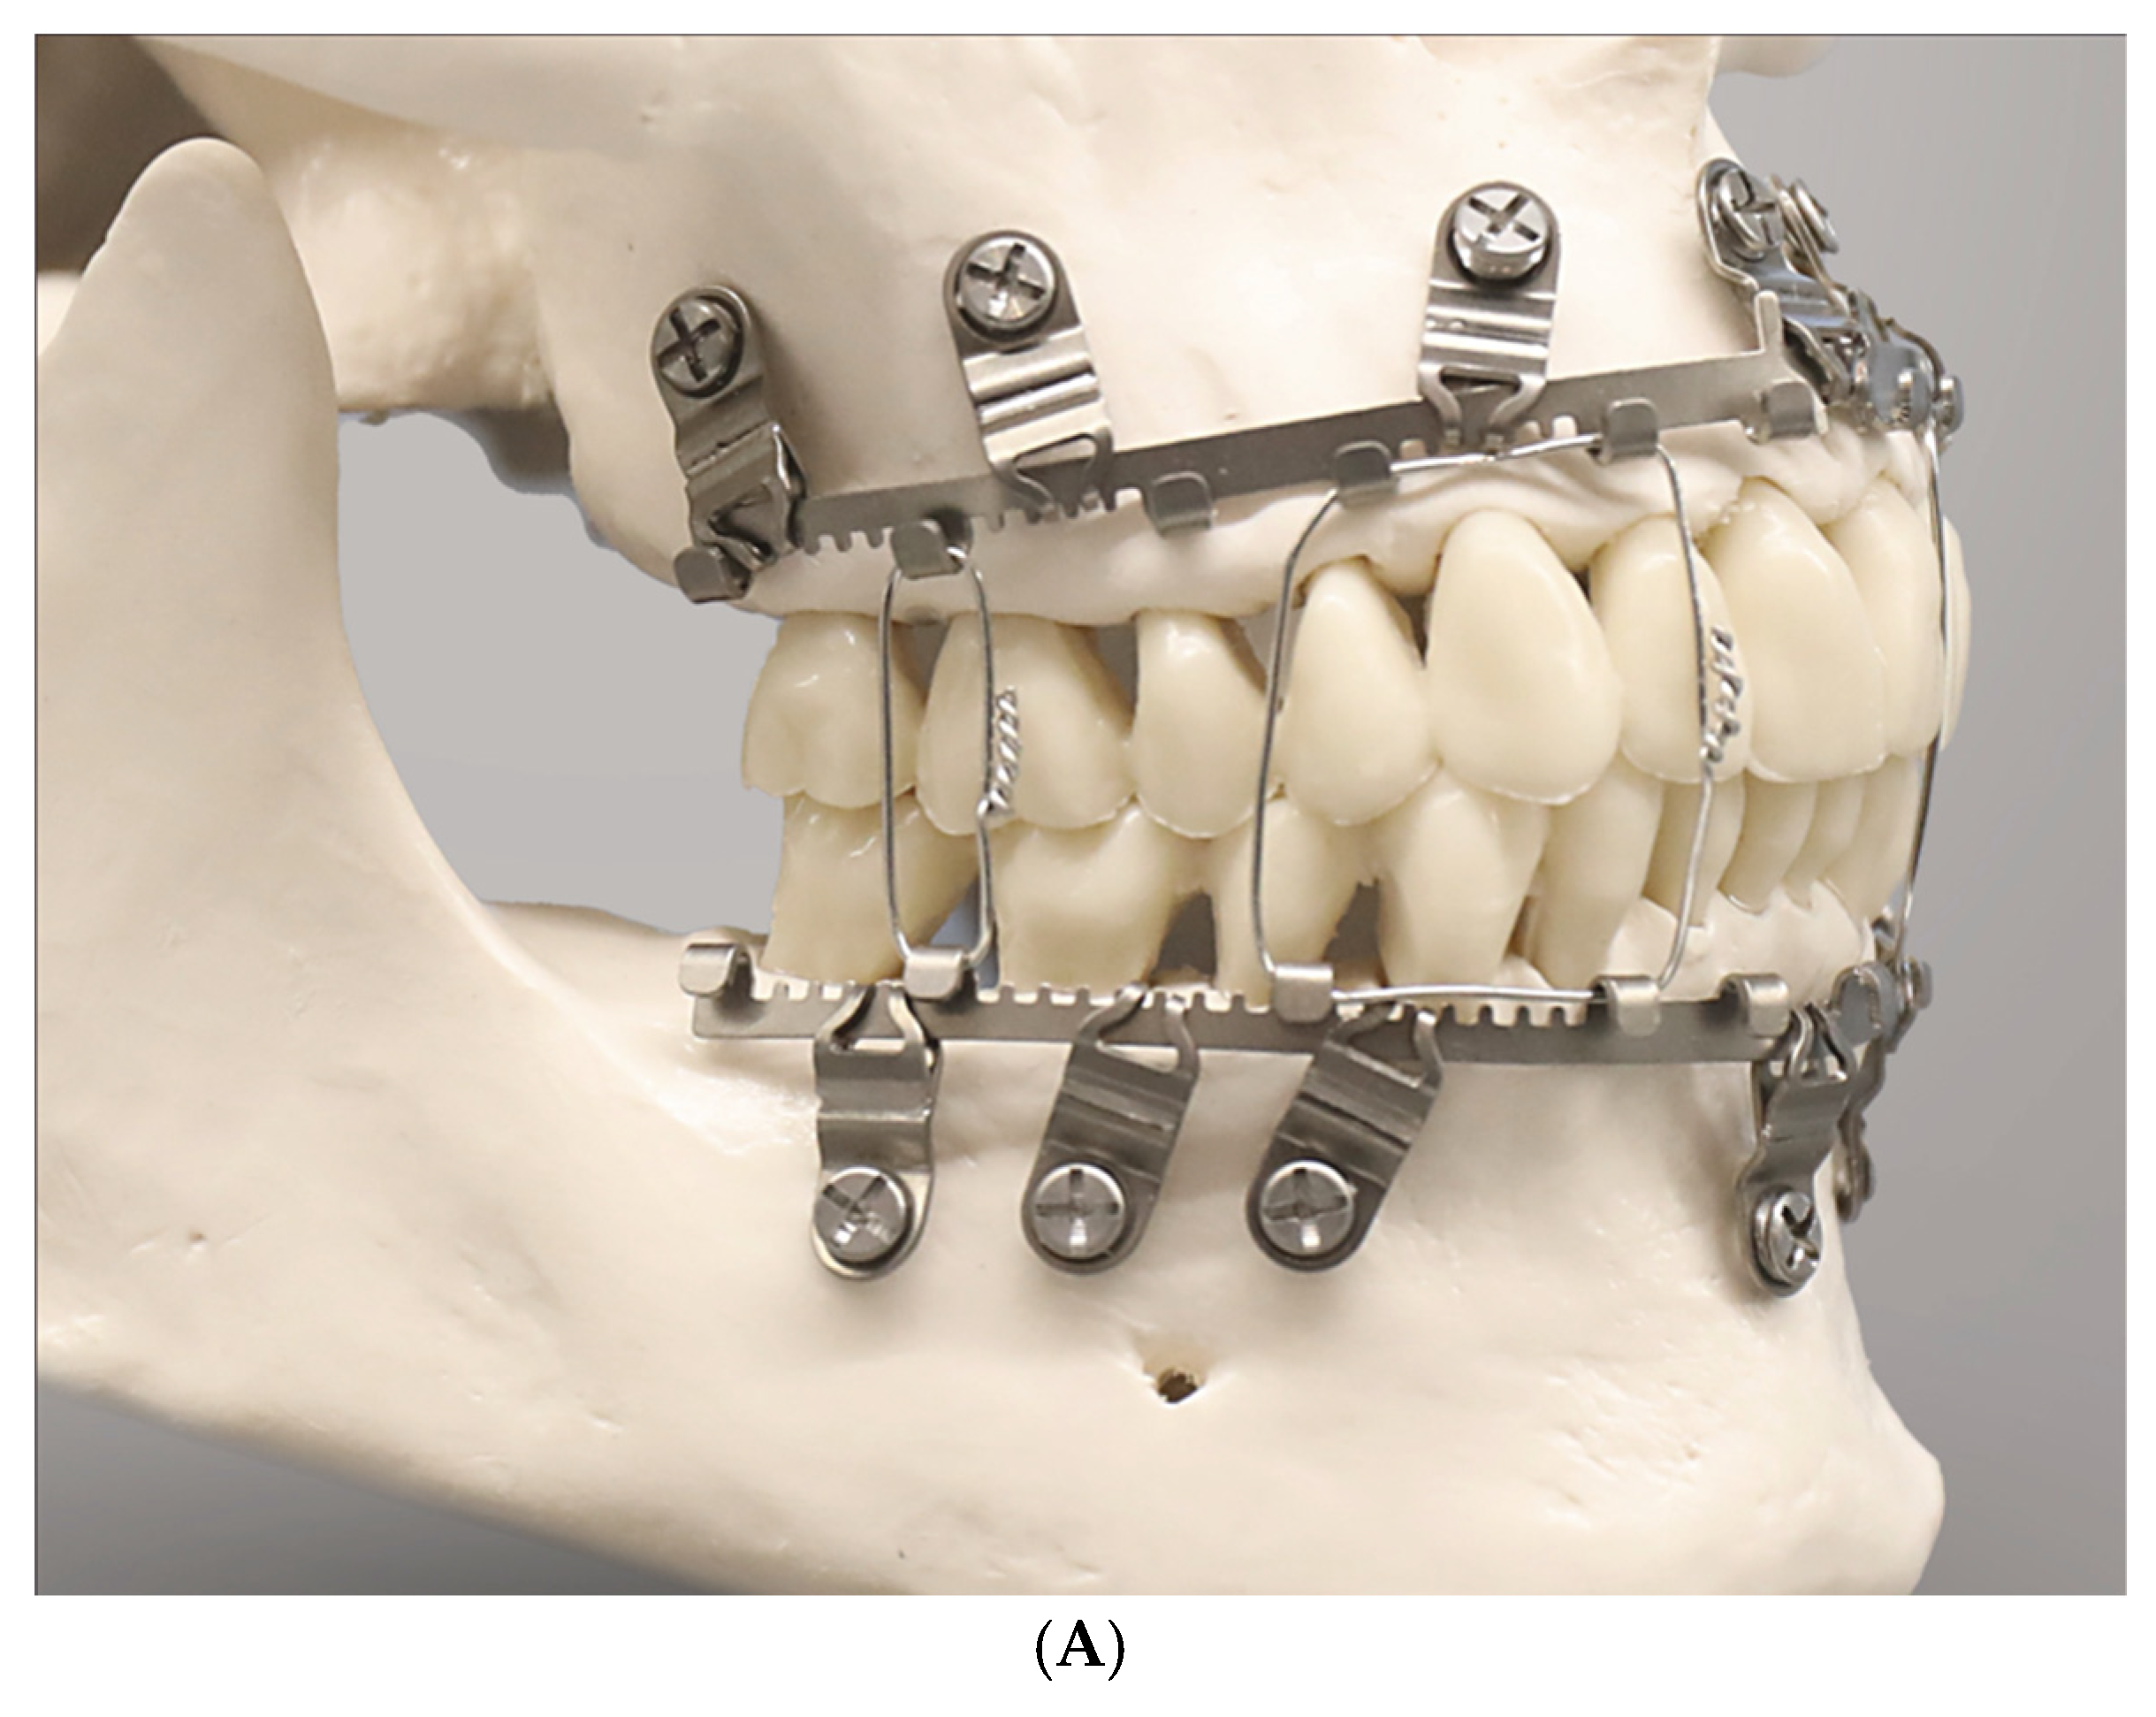

The SMARTLock Hybrid MMFTM System (Stryker Inc., Kalamazoo, MI, USA) was licensed from J.R. Marcus (US Patent No. 8118850—21 February 2012 [13], Marcus and Powers 2016 [14]).

It was the first commercially available—US FDA-approved—hybrid or bimodal MMF device on the international market with a framework made of thin malleable Titanium.

The innovative feature of a SMARTLock System is blade-like legs which project perpendicular from the hookless edge of the longitudinal arch bars. The ends of these support legs contain holes to secure the device into the alveolar bone with 2.0 optimized self-drilling locking screws of 6 mm or 8 mm length.

The supporting legs or hinges featuring a hole are regularly addressed as ‘lugs’.

The longitudinal bar segments are studded with nine supporting lugs able to serve as bone anchorage points.

The lugs are bendable and can be adjusted to face their openings over the interradicular spaces for transmucosal monocortical screw insertion.

The locking mechanism is obtained by a bone screw with a threaded conical locking head below the screw head and above the screw shaft. The screw-receiving hole in the lugs accommodates a single matching top countersunk hole into which the cones of the screw engage successively during insertion to hold the plate at an elevated level above the oral mucosa, creating a “Standoff”. A plate spacer fork can be used for assistance. Currently, the SMARTLock Hybrid MMFTM System bar element comes in a regular size (gold-colored) with relatively prominent lugs (Figure 2A,B) and a smaller, low-profile version (silver-colored) with attenuated, less projecting, lugs (Nizam and Ziccardi 2014 [15], Chao and Hulsen 2015 [16], Kendrick et al. 2016 [17], Kendrick and Park 2016 [18], Stryker SMARTLock Brochure—Last internet access February 2025).

The position of the openings in the lugs allows leaning the arch bar against the tooth equators in the manner of a fence and to bridge the attached gingiva up to the mucogingival line. The construct is then secured with screws, ideally inside the zone of the attached gingiva.

SMARTLock MMF System

The flat band shaped configuration with incorporated hooks along one edge of the Erich arch bar serves as the blueprint for the embodiments of the three systems (Figure 7, Figure 8, Figure 9 and Figure 11).

This becomes overt at the first glance at the SMARTLock Hybrid bar (Figure 7).

The conventional Erich arch bar serving as the basic structural SMARTLock constituent is equipped with multiple “lugs” (Figure 2A, Figure 7 and Figure 8).

To target the desired point for insertion of a bone screw, the lugs can be bent around an arch of rotation. Moreover, the lugs can be extended along their vertical axis by either flattening or steepening the angled footing portion (buckling) of the lug. Doing so, however, can alter the standoff from the mucosal surface.

The range of these movements is controlled by the vertical height of the lug and its material properties. Geometrically, these potential movements cover a crescentic surface area (Figure 8).